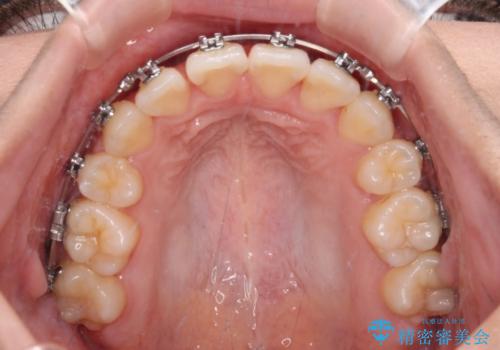

- メタルブラケット

- 1年6ヶ月

- 10-30回

舌の突出癖によるオープンバイトになっていたため、インビザラインによるマウスピース矯正をおすすめしましたが、自己管理の自信がないとのことで、ワイヤー装置による矯正治療を行うこととしました。